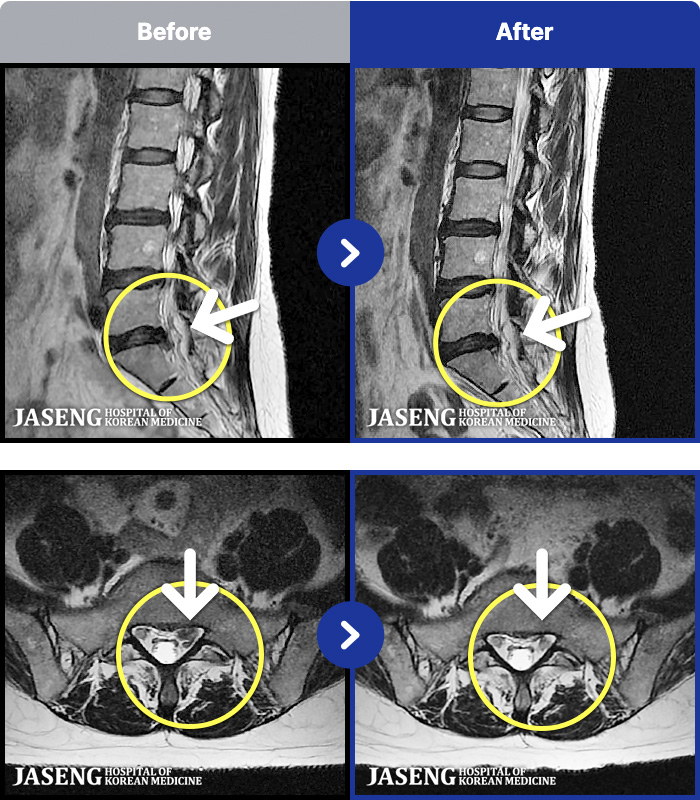

54 MRI ũ ʸ Ȯϼ.

ȯںп Ǹ ǿ ԿǾ, ο ġ ۿ Ƿ ġḦ Ͻñ ٶϴ.